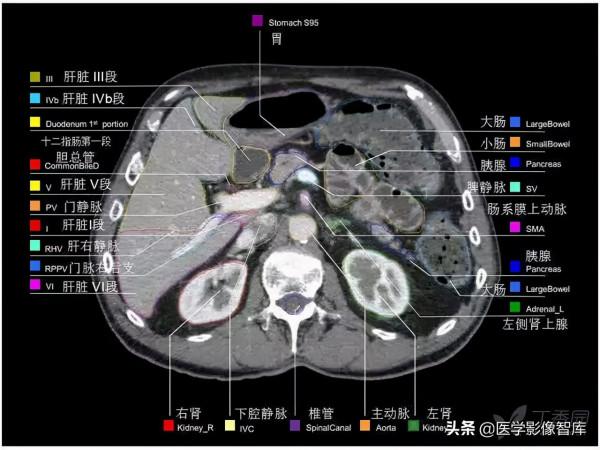

腹部CT